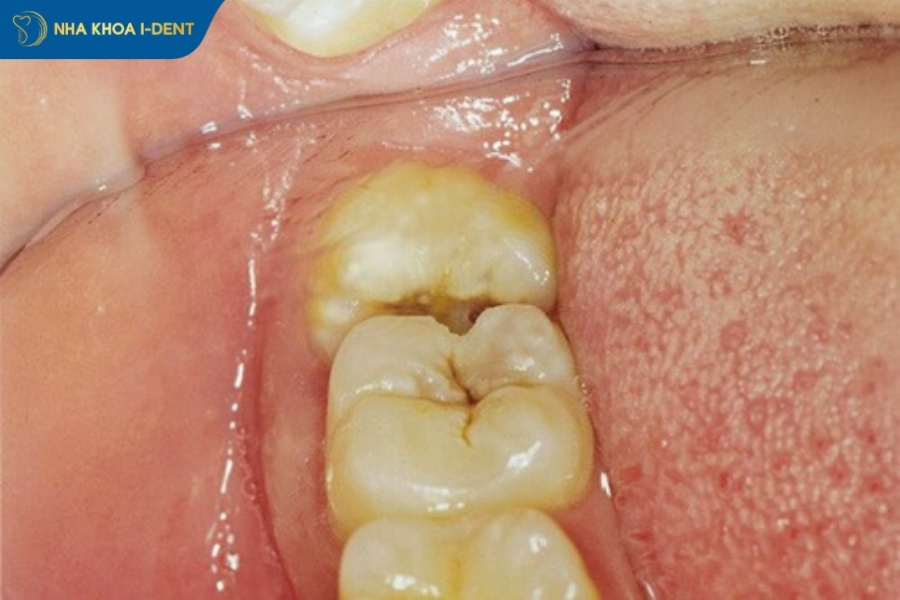

Răng khôn mọc lệch không nhổ sẽ dẫn đến nhiều vấn đề như khó vệ sinh và không thể làm sạch răng, tạo áp lực lên các răng khác làm ảnh hưởng các răng lân cận. Điều này sẽ dẫn đến sâu răng số 7, viêm nướu, hôi miệng, xô lệch hàm, áp xe hoặc u nang xương hàm.

- Gây sâu răng số 7 và các răng lân cận do răng khôn mọc lệch đâm vào răng số, tạo khe giắt thức ăn khó vệ sinh.

- Gây hôi miệng vì răng khôn mọc lệch khó vệ sinh, gây giắt thức ăn làm tích tụ vi khuẩn dẫn đến viêm nướu, lợi trùm và chảy mủ.

Răng khôn mọc lệch gây giắt thức ăn.